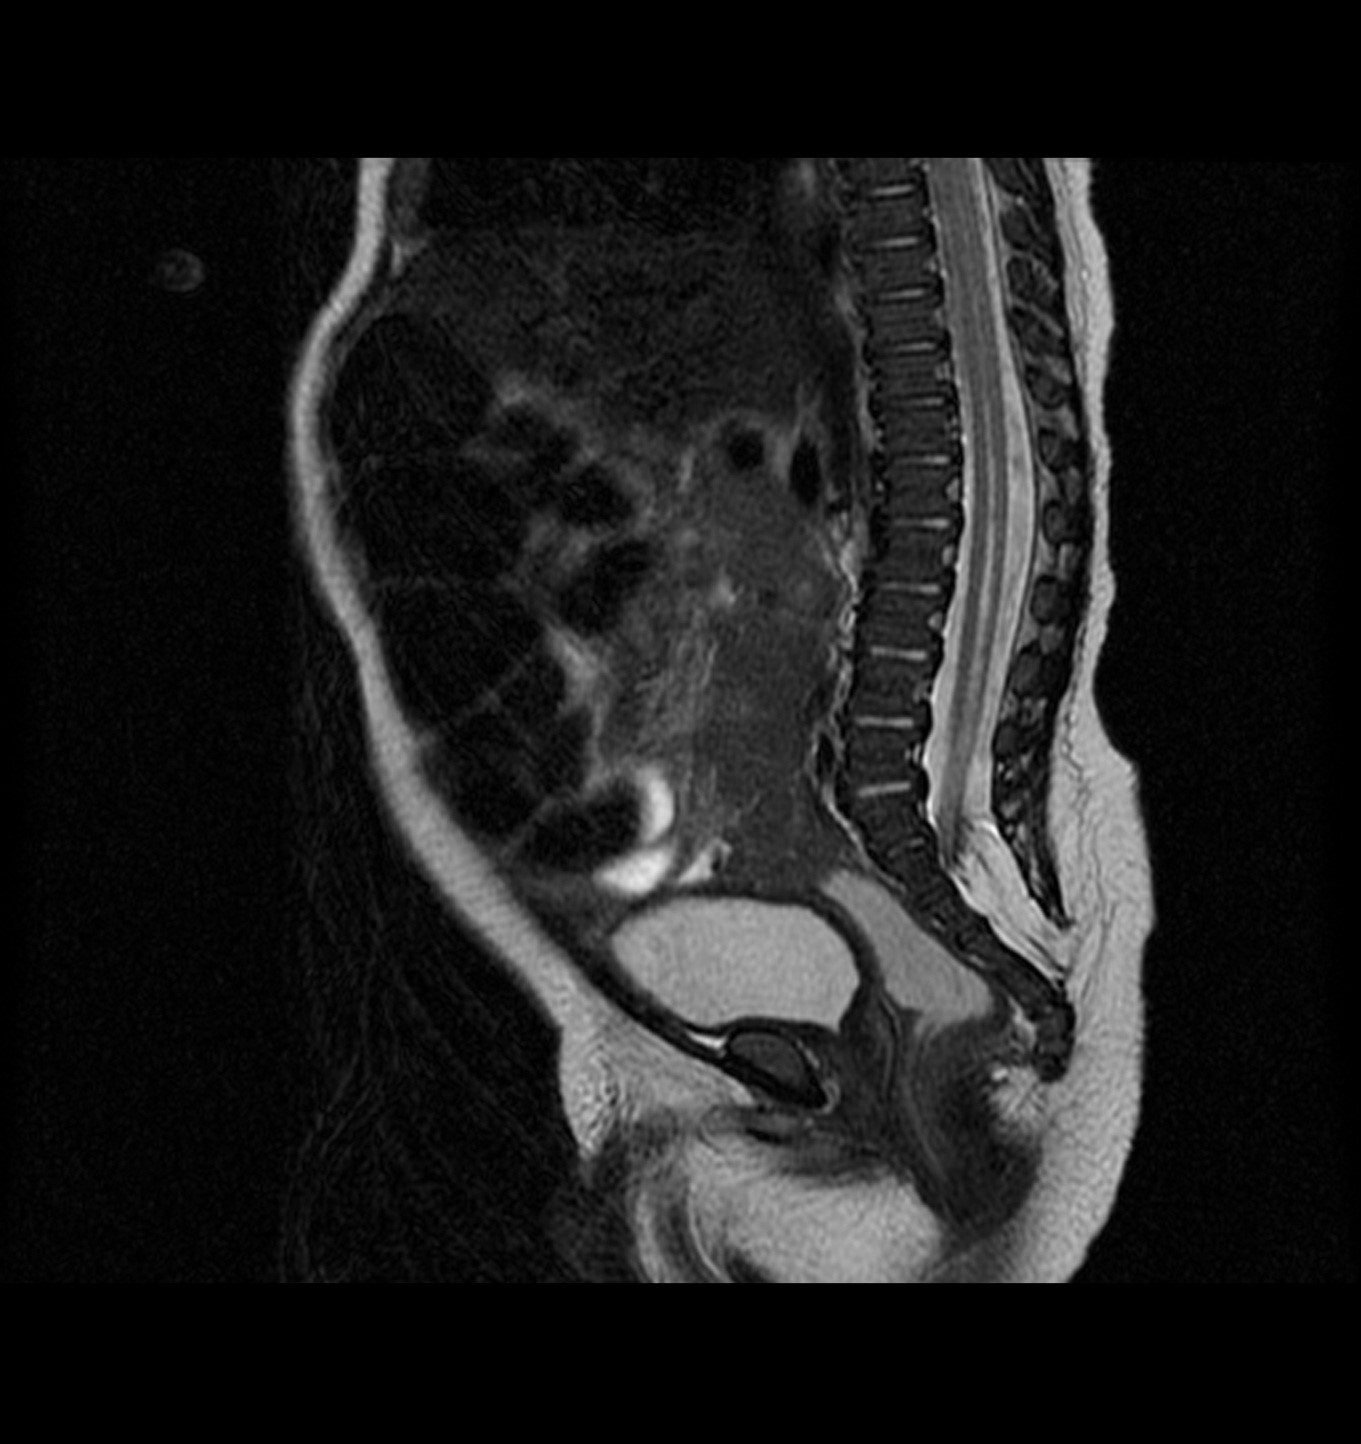

Ante la sospecha de DEO, se solicita ecografía de la zona, en la que se observa lesión compatible con lipoma asociado a disrafismo. Posteriormente se realiza resonancia magnética (RM) de columna, que confirma una lesión compatible con “lipomielocele con médula anclada a nivel S1 y siringomielia” (Fig. 2).

| Figura 2. RM lumbosacra, corte sagital en T2. Lipoma que se extiende desde tejido celular subcutáneo hasta cono medular. Dilatación del canal centromedular |